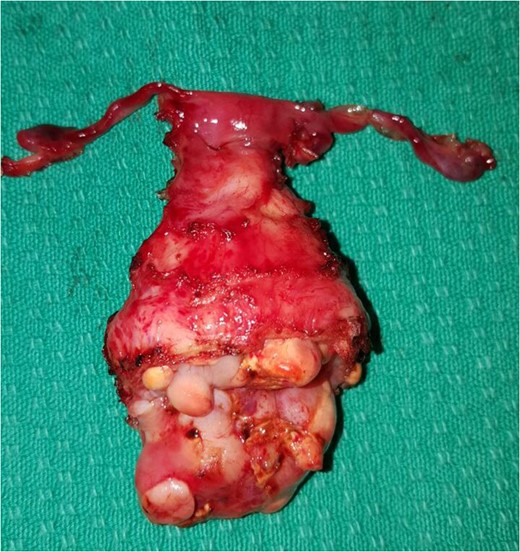

Total abdominal hysterectomy, bilateral salpingectomy with upper vaginectomy.

The Histopathological examination of the specimen revealed residual Embryonal RMS, Botryoid type. Most of the tumor mass show fibrosis, histiocytic inflammation and hemosiderin deposition, consistent with treatment effect.

The optimal number of adjuvant chemotherapy cycles needed varies; it depends upon the clinical and radiological response. There are many reports of neoadjuvant chemotherapy being used to shrink large tumors before the surgery [5]. In this case, a neoadjuvant therapy was used of which 10 cycles of VAC protocol (vincristine, d-actinomycin and cyclophosphamide) were given. The VAC protocol is the most widely used chemotherapy regimen in RMS [4]. After the proven response to neoadjuvant chemotherapy; surgery was uneventful in the form of total abdominal hysterectomy, bilateral salpingectomy, upper vaginectomy (Fig. 3), ureterolysis and bilateral ovarian transposition (oopexy), the oopexy is to preserve the ovarian function knowing that she may receive radiation therapy too. Over the decades, there has been a paradigm shift in management strategies for botryoid RMS. Although ultra-radical surgery i.e. pelvic exenteration was considered the treatment of choice in the late 1960s, outcomes were often unsatisfactory. In the 1970s, limited surgery with adjuvant chemotherapy and/or irradiation showed improved survival [6].